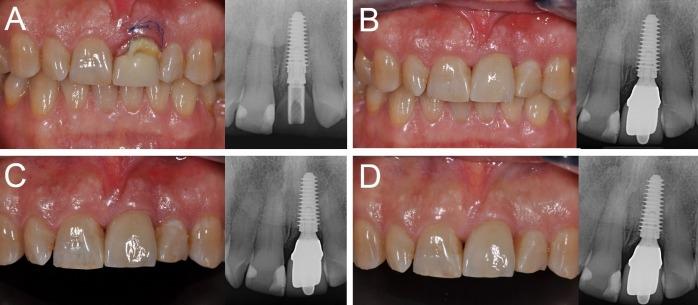

在当前的科学文献中,关于单个种植体即刻功能负载的研究很少。本研究的目的是评估植入愈合牙槽嵴和新鲜拔牙位点的即刻负载单个种植体的4年生存率、并发症发生率和种植体周围边缘骨吸收(PIMBL)情况。六个中心参与了这项前瞻性研究。在开始招募患者之前,详细定义了手术和修复方案。患者招募和手术于2012年2月至2013年2月期间进行。纳入标准为愈合牙槽嵴和新鲜拔牙窝中的单牙间隙。所有种植体(Anyridge®,韩国庆尚北道Megagen公司)在植入后即刻进行功能负载,并随访4年。观察指标为种植体生存率、并发症和PIMBL。选择了46例患者(年龄18 - 73岁)。总共植入了57颗种植体(10颗植入新鲜拔牙窝)。经过4年的功能负载,仅一颗种植体丢失;因此,报告了较高的生存率(基于患者为97.6%;基于种植体为98.1%)。此外,报告的生物学并发症(基于患者为4.8%;基于种植体为3.8%)和修复并发症(基于患者为9.7%;基于种植体为7.6%)发生率有限。4年总的PIMBL为0.38±0.21 mm(愈合牙槽嵴:0.4±0.21 mm;新鲜拔牙窝:0.33±0.20 mm)。即刻负载单个种植体似乎是一种非常成功的治疗方式。然而,需要长期数据来证实这些积极结果。

https://cdn.ncbi.nlm.nih.gov/pmc/blobs/87a2/5928471/e3b97f58994e/joddd-12-26-g004.jpg

https://cdn.ncbi.nlm.nih.gov/pmc/blobs/87a2/5928471/e952139cd01e/joddd-12-26-g001.jpg

https://cdn.ncbi.nlm.nih.gov/pmc/blobs/87a2/5928471/7ba5040a8f0a/joddd-12-26-g002.jpg

https://cdn.ncbi.nlm.nih.gov/pmc/blobs/87a2/5928471/21c584e33dfc/joddd-12-26-g003.jpg